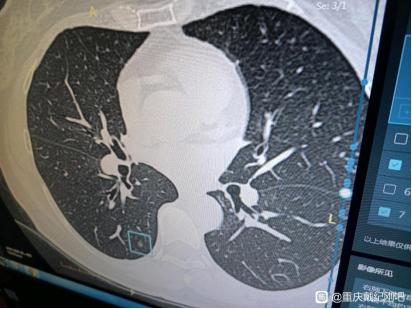

今天这位患者的情况是比较特殊,因为她的四个混合性磨玻璃结节其实都比较小,最大才5mm。但是四个结节术后大病理却都已经是微浸润腺癌了,复查三次当地医院都说还小,不用管他。患者找到我面诊之后,我当即判断可能已经是微浸润腺癌了,但再随访一段时间可能也是安全的。患者心理压力非常大,无法安心随访。患者很信任我,说把医保都已经提前迁到了重庆,但是其实像这种结节越小,越不好手术,很容易漏诊漏切,很容易在手术中就根本找不到目标结节,切掉的是疑是结节而漏掉目标结节。但在我这里,这些难题都是可以“手拿把攥”的,把只要有危险的肺结节一网打尽,才是我的风格。

在给爸爸陪床期间,我也做了肺CT,显示有小结节。医生叮嘱我,三个月复查就可以。复查了3次后,医生都说芝麻大小的结节,不用管它。在新桥医院做的高分辨CT,有4个结节。

检查完成,11号手术。手术后,家人接到戴主任的短信,激动万分:手术非常成功,刚结束。右肺下叶结节1至少原位,结节2和结节3微浸润性腺癌,右肺上叶结节微浸润性腺癌。都是早早期的,切干净了,治愈了。

这4个小的混合性磨玻璃结节,最大0.5cm,最小0.3cm,在当地医院,手术只能切除最大的。那么,留下任意一个,都将是致命的。看了混磨再小,也不能掉以轻心。